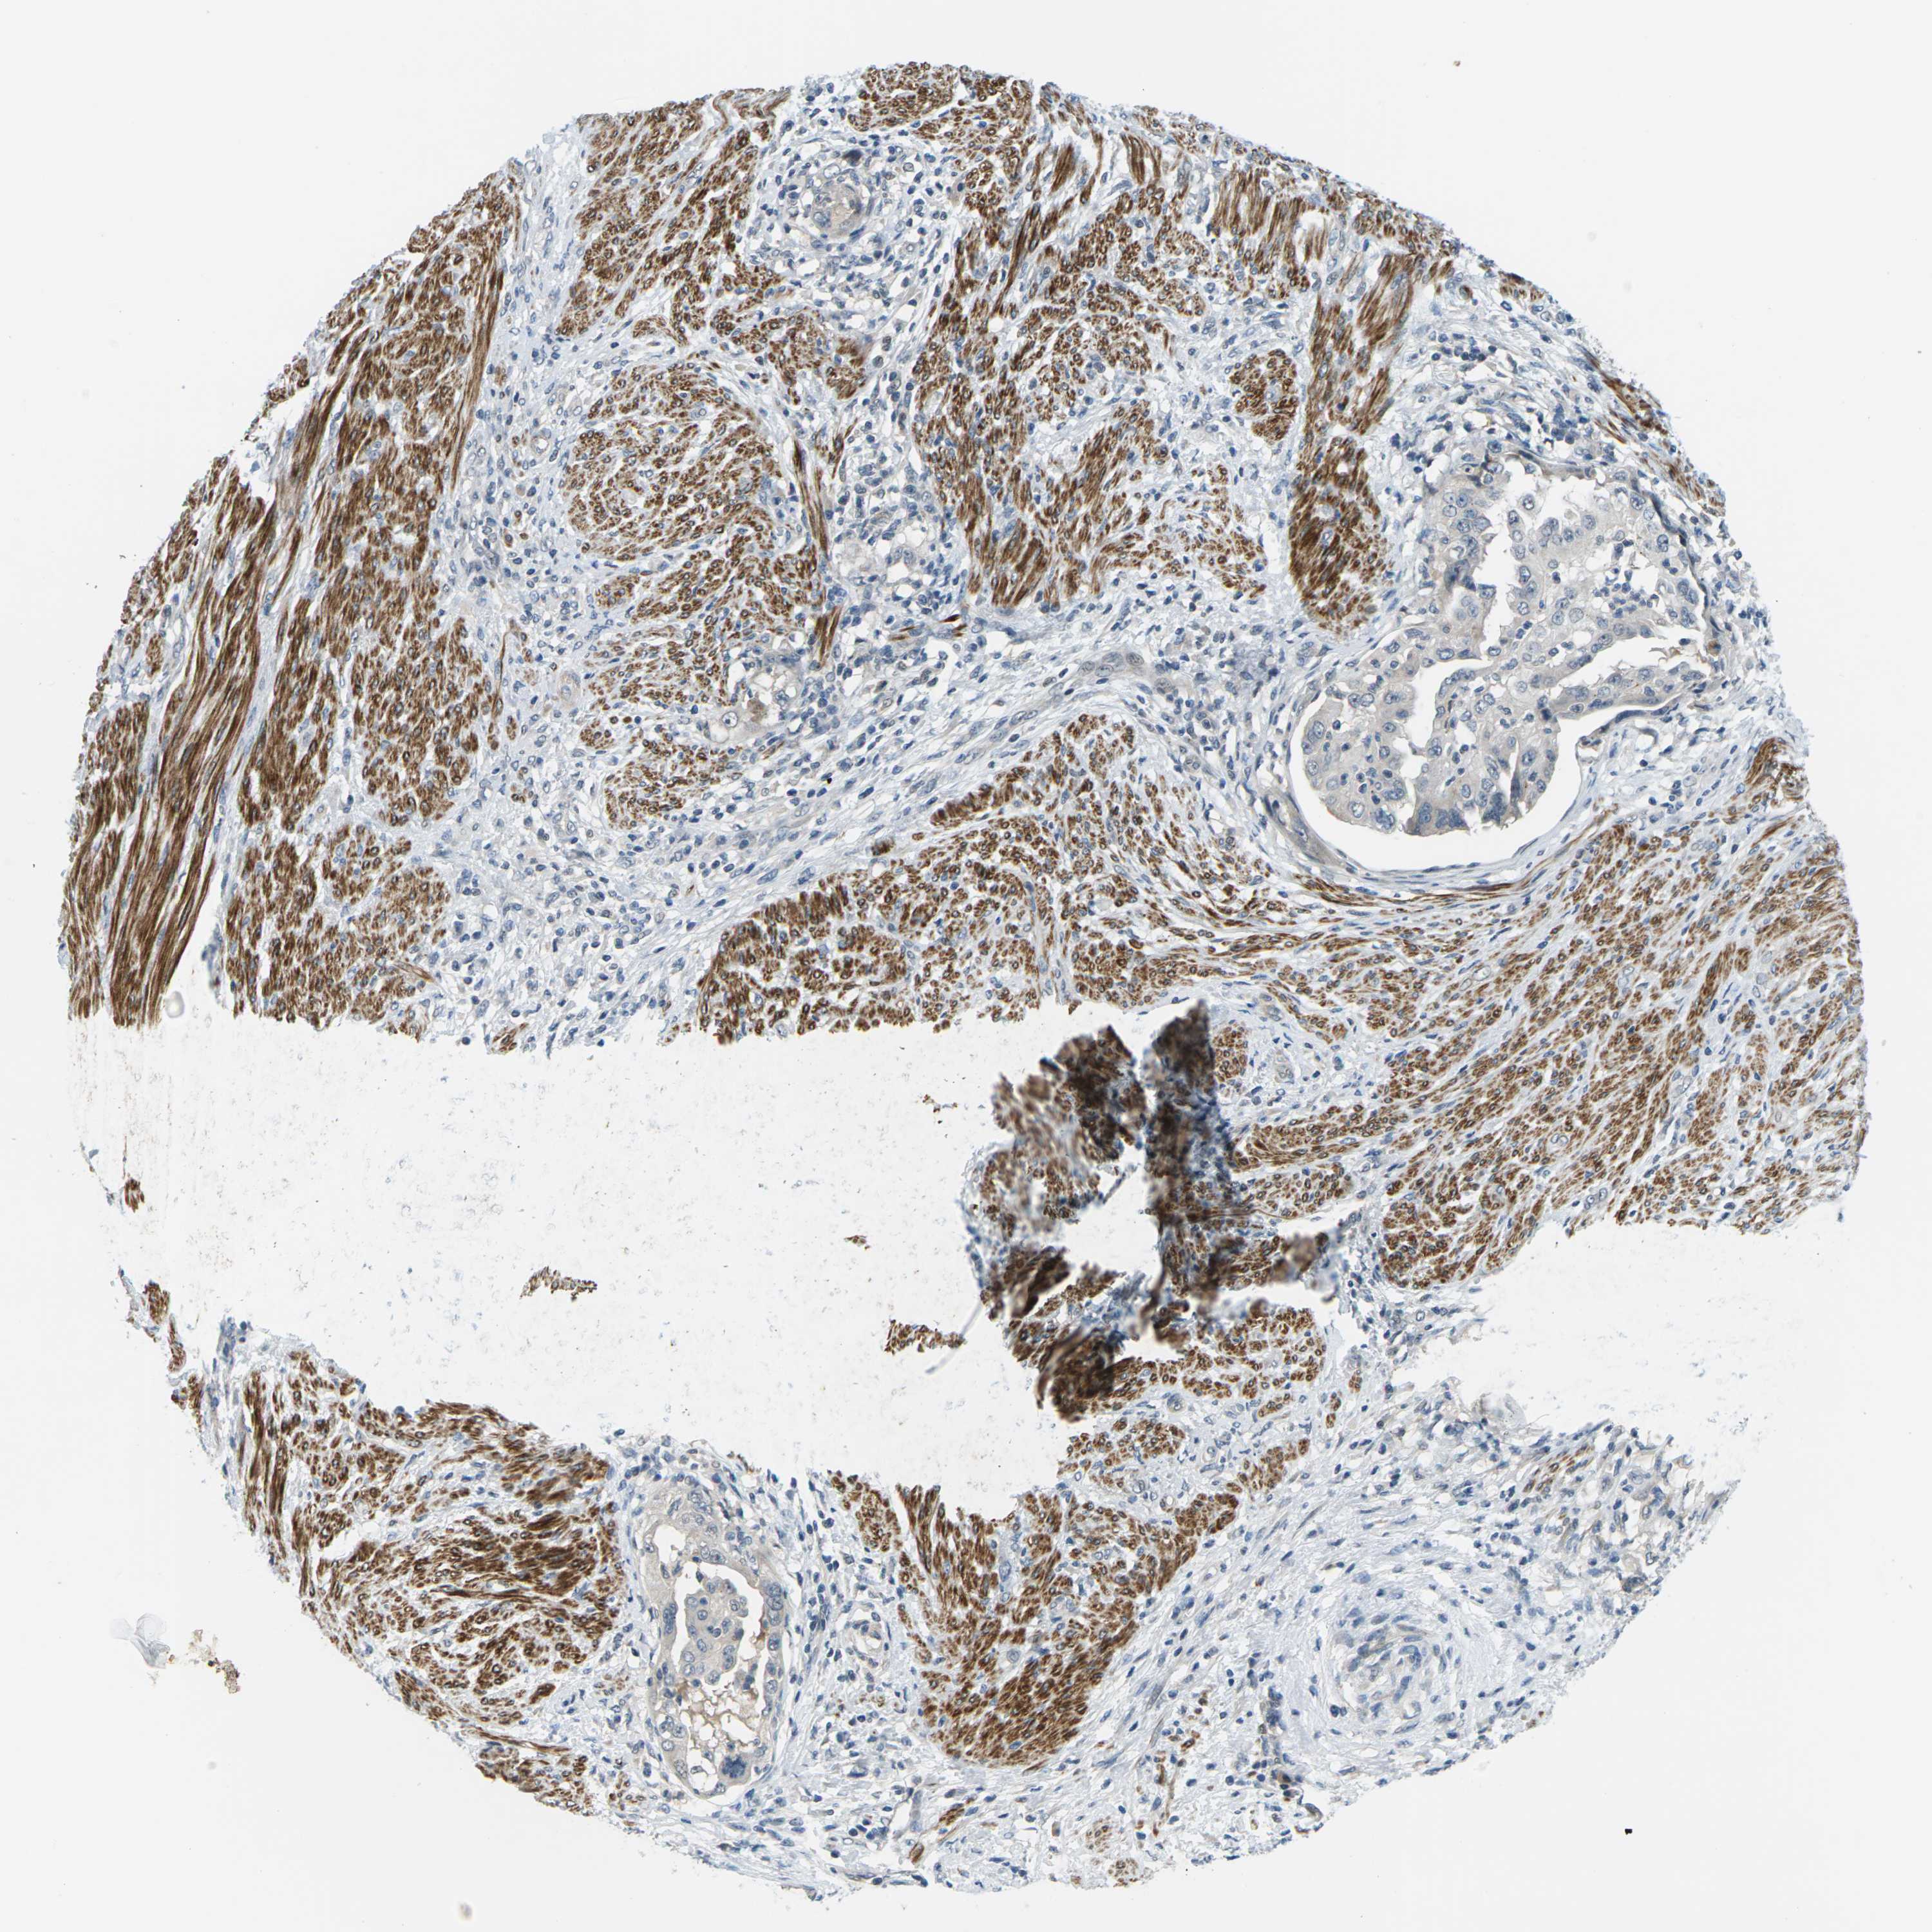

ENDOMETRIAL CANCER - Protein expressioni

A mouse-over function shows sample information and annotation data. Click on an image to view it in a full screen mode. Samples can be filtered based on level of antibody staining by selecting one or several of the following categories: high, medium, low and not detected. The assay and annotation is described here.

Note that samples used for immunohistochemistry by the Human Protein Atlas do not correspond to samples in the TCGA dataset.

Antibody stainingi

Antibody staining in the annotated cell types in the current human tissue is reported as not detected, low, medium, or high, based on conventional immunohistochemistry profiling in selected tissues. This score is based on the combination of the staining intensity and fraction of stained cells.

Each image is clickable and will lead to virtual microscopy that enables deeper exploration of all samples and also displays staining intensity scores, fraction scores and subcellular localization as well as patient and tissue information for each sample.

Antibody HPA014353

Antibody HPA014736

Staining

High

Medium

Low

Not detected

Intensity

Strong

Moderate

Weak

Negative

Quantity

>75%

75%-25%

<25%

None

Location

Nuclear

Cytoplasmic/membranous

Cytoplasmic/membranous,nuclear

Adenocarcinoma, NOS